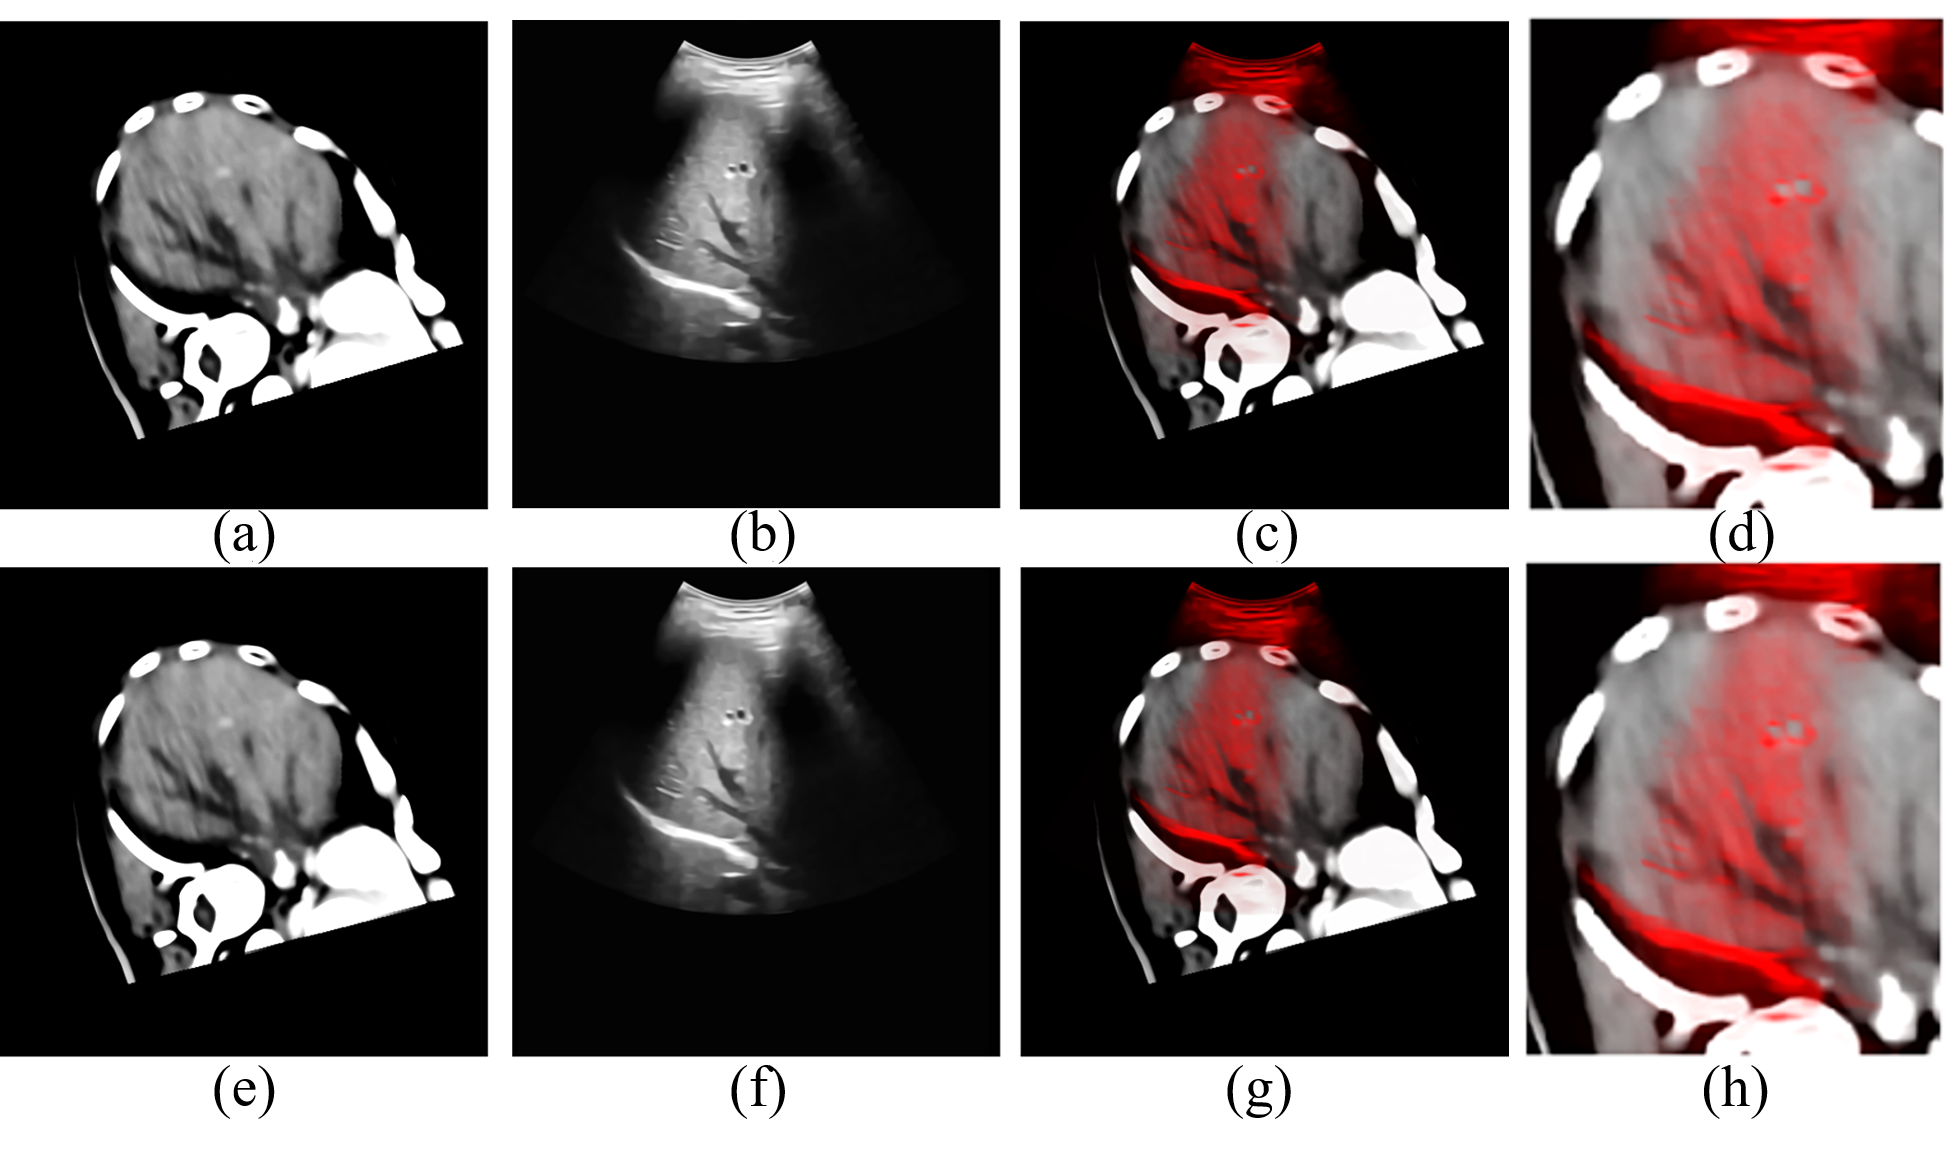

Refer to caption

Figure 4: The data before and after registration of test 2. (a) is the corresponding CT slice of the original ultrasonic image (b) after the matching of world coordinate system. (e) is the result of the rigid registration from CT volume data to ultrasonic image. (f) is the non-rigid registration result of the ultrasonic image (b). (c) and (g) are the fusion image of (a) (b) and (e) (f), (d) and (h) are the details of (c) and (g), respectively.

The data before and after the registration are shown in Fig. 3-5, where subfigures 3(a), 4(a) and 5(a) are CT slices corresponding to original ultrasonic images, subfigures 3(b), 4(b) and 5(b) after the matching of the world coordinate system. Subfigures 3(e), 4(e) and 5(e) are CT slices after rigid registration to original ultrasonic images, and subfigures 3(f), 4(f) and 5(f) are non-rigid registration results of original ultrasonic images to their correspondence rigid registered CT slices. And fusion images of CT slices and ultrasonic images before and after registration are obtained and shown in Figs. 3(c) – 5(c) and 3(f) – 5(f) to better evaluate our algorithm. According to these figures, on comparison with the fusion image before registration, boundaries of both the liver and vessels are better matched. And the positions and shapes of vessels are also corrected. And the positions of bones in Figs. 4(g) and 5(g) are also closer to their positions in the ultrasonic images, which can be inferred by their “shadows” in the ultrasonic image.

The details of results in Figs. 3-5 are shown in subfigures (g) and (h) of Figs. 3-5, which also show that our registration algorithm can improve the matching accuracy between the CT data and ultrasonic images, especially in the parts pointed by arrows in Figs. 3 and 4. However, although our algorithm has better registration performances than the Demons algorithm, there still exists some parts that can be improved, such as the places pointed by the blue arrow in Fig. 4(h) although the distance between points A2 and B2 is shorter than that between points A1 and B1, points A2 and B2 are still not matched.